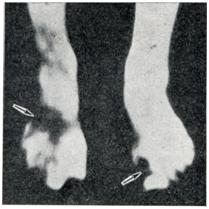

Рис. 16

Инфракрасные термограммы рук: а— при отморожении пальцев и кистей в раннем реактивном периоде (дистальные отделы пальцев не выявляются, термограмма носит характер ампутационной); б— термограмма рук здорового человека.

Для получения информации об Ordo Deus откройте новое окно. Перейти в оглавление

Рис. 17.

Инфракрасная термограмма ног в стадии развития воспаления после отморожения стоп: видно повышенное излучение стоп (светлые зоны) и участки подавленного излучения пальцев (темные зоны)

Уже в первые недели после отморожения (то есть раньше, чем каким-либо другим методом) с помощью инфракрасной термографии удается выявить зоны, подвергающиеся деструктивным процессам. На термограммах они определяются в виде участков ослабленной или подавленной радиации на фоне интенсивного излучения областей, захваченных реактивным воспалением (рис. 18). С помощью цветной термографии при отморожении возможна точная характеристика нарушения циркуляции в пораженных тканях. При этом поля различных изотерм определяются цветом, и граница нежизнеспособных и плохо снабжаемых кровью тканей выявляется весьма четко (рис. 11).

С помощью инфракрасной термографии при отморожениях можно не только определять зоны омертвения тканей, выявлять участки с пониженной реактивностью вследствие расстройства циркуляции (что имеет большое значение для определения уровня некрэктомии или радикальной ампутации), но и контролировать эффективность лечения.

Рис. 18.

Инфракрасная термограмма ног через 2 недели после отморожения пальцев и стоп: подавленное излучение в проксимальных отделах стоп, подвергающихся деструкции (указаны стрелками), наряду с интенсивным излучением очагов, захваченных реактивным воспалением.